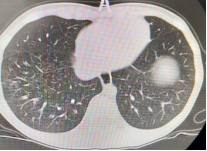

以下為呼吸專業(yè)典型病例分享:

圖片5:氣管內(nèi)膜結(jié)核及重癥支原體肺炎所致氣道阻塞、塑性支氣管束